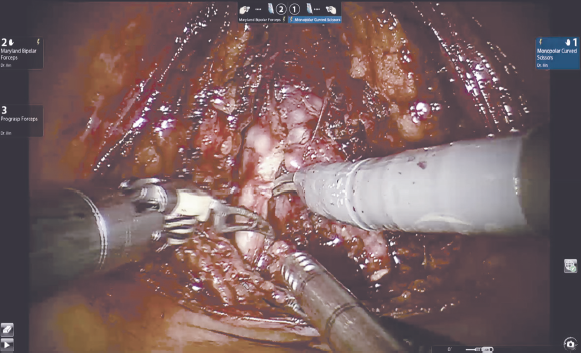

Вскрытие париетальной брюшины в проекции шейки мочевого пузыря. Операция выполняется трансперитонеально, расположение роботических троакаров повторяет таковое при традиционном доступе. Ассистентские 12- или 5-миллиметровые порты также устанавливаются стандартно: параректально справа на 2–3 см выше оптического порта и на 6–8 см латерально от правого роботического порта соответственно. На первом этапе происходит вскрытие париетальной брюшины. В отличие от традиционного доступа, инцизия производится в проекции шейки мочевого пузыря, а не его верхушки. Для лучшей визуализации третьим роботическим инструментом осуществляется тракция задней стенки мочевого пузыря вверх. Выделение семявыносящих протоков и семенных пузырьков (рис. 1). Этот этап операции выполняется сразу после вскрытия париетальной брюшины. Техника диссекции семявыносящих протоков и семенных пузырьков не отличается от стандартной. Основным фактором, обеспечивающим техническую сложность этого этапа, является небольшой объем операционного поля и невозможность выполнения широких тракций семенных пузырьков и самой предстательной железы, которая на данном этапе остается выделенной лишь на небольшой поверхности ее основания. Выделение задней поверхности простаты и сосудисто-нервных пучков (рис. 2), как и при традиционном доступе, происходит после этапа выделения семенных пузырьков. Уровень нервосбережения определяется на основании стадии опухолевого процесса. Для доступа к заднелатеральным отделам предстательной железы выполняется частичная латеральная диссекция пузырно-простатических мышечных волокон. Диссекция шейки мочевого пузыря (рис. 3) выполняется в направлении снизу вверх и является одним из самых сложных шагов этой операции. На этом этапе в наибольшей степени проявляется преимущество свободно изгибающихся на концах роботических инструментов. Для лучшей визуализации используется развернутая наверх (30°) оптика. Шейка мочевого пузыря вскрывается по задней поверхности, уретральный катетер извлекается, после чего рассекается передняя ее поверхность. Диссекция дорзального сосудистого комплекса производится тупым и острым путем без предварительного прошивания и перевязывания. После выделения верхушки простаты железа отсекается от уретры. На этом этапе при необходимости производится прошивание элементов дорзального комплекса. На рис. 4 представлено ложе удаленной предстательной железы. Наложение пузырно-уретрального анастомоза (рис. 5) начинается с передней его стенки на 12 ч условного циферблата. Анастомоз выполняется с использованием самозатягивающихся нитей. Сложность этого этапа обусловлена, в основном, непривычной визуализацией. Ввиду того, что мобилизация мочевого пузыря не производилась, сопоставление слизистой уретры и мочевого пузыря происходит без видимого натяжения, поэтому усиления соустья с помощью дополнительной реконструкции не требуется. При необходимости выполняется задняя пластика шейки мочевого пузыря. Последним этапом производится установка дренажа к зоне анастомоза и ушивание париетальной брюшины.

Рис. 3. Диссекция шейки мочевого пузыря

Fig. 3. Dissection of the neck of the bladder